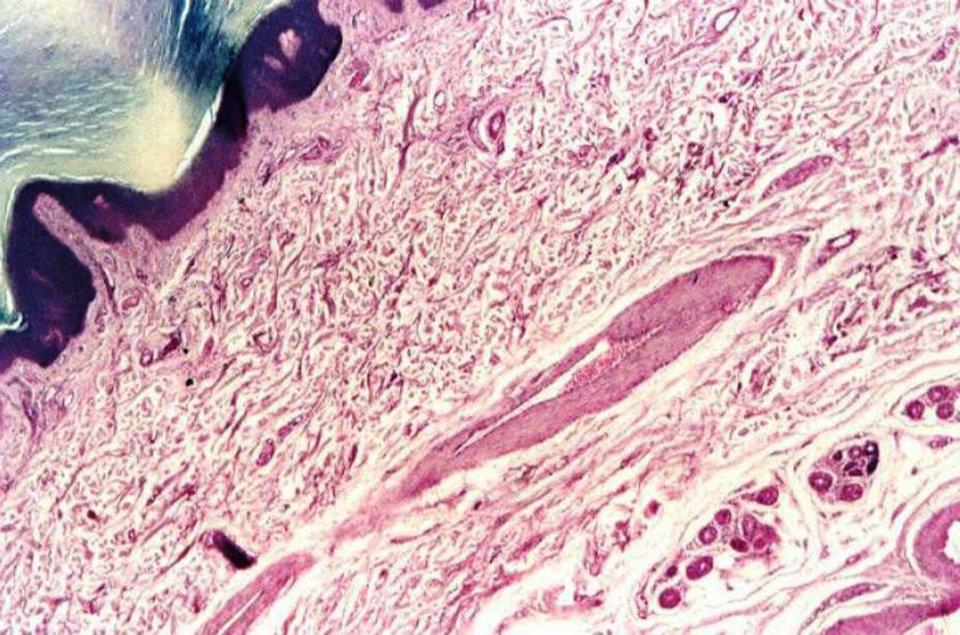

Piel epitelio plano estratificado QUERATINIZADO - epidermis; gl.

tubulares simples enrrolladas - gl. sudoríparas; gl. holocrinas - gl.

sebáceas) - H/E

Los epitelios planos estratificados varían en grosor dependiendo del

número de capas celulares presentes. Las células más profundas, que

están en contacto con la membrana basal, son de forma cubica o

cilíndrica. Esta capa es usualmente llamada de células basales. Las

células basales son mitóticamente activas y reemplazan las células del

epitelio que se pierden durante la descamación normal del epitelio. A la

capa de células basales le sigue capas de células con contornos

poliédricos. Cerca de la superficie del epitelio, las células se vuelven

aplanadas. En la superficie del epitelio las células parecen escamas

planas - de una manera similar a las células epiteliales del epitelio

plano simple.Recuerda que es la forma de las células que forman la superficie del epitelio, la que da el nombre morfológico al epitelio.